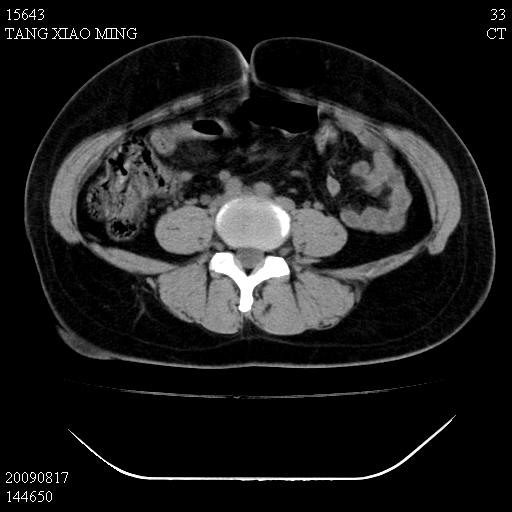

标题: CT21692:盆腔病变

女,33岁,右下腹痛2年余,既往宫外孕病史,如在我院手术,结果下周公布,

可能的诊断。1子宫内膜异位【子宫腺肌症并右卵巢巧克力囊肿】;2 右卵巢囊腺瘤。子宫肌瘤

1)考虑卵巢巧克力囊肿,不排除卵巢囊腺瘤。2)子宫肌瘤可能。

卵巢囊腺瘤,子宫肌瘤,直肠壁厚,不除外占位.